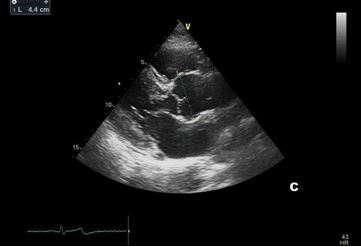

In our patient transthoracic echocardiography revealed normal diameters of the left ventricle with mild septal hypertrophy (EDD: 51 mm; ESD: 31 mm; IVS: 12 mm; PW 10 mm) with mild enlargement of the right ventricle (mid-cavity diameter: 37 mm), with normal biventricular systolic function. However, TTE revealed a tricuspid aortic valve with dilatation of the aortic root (44 mm, Z-score >2: Z=4.2). Ascending Aorta and aortic arch diameters were normal in absolute values (35 mm and 32 mm, respectively) and when keeping into consideration body size.

After a year, our patient underwent TTE that showed an aortic root dimension of 44 (Figure C), stable in comparison with the previous evaluation, with no modification of ascending aorta measurement and no LV enlargement (Figure A and B). He continues with yearly follow-up, continuing with personalized physical activity previously prescribed.